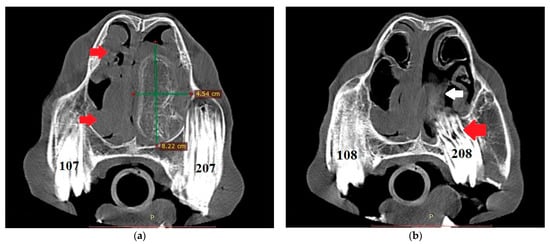

The endoscopic examination of the right nostril revealed the rightward bending of the nasal septum; an examination of the left side was unavailable due to the presence of the mass. Computed tomography of the head was performed under general anesthesia in dorsal recumbency. The patient was sedated with detomidine (0.02 mg/kg) prior to anesthetic induction with diazepam (0.1 mg/kg) and ketamine (2.2 mg/kg). Anesthesia was maintained using isoflurane (induction 5%, maintenance 2–3%). CT images were acquired with a Revolution 750 CT scanner, GE Healthcare Corporation, Chicago, IL, USA (120 kV, 280 mA, at 1.3 mm slice thickness). Two-dimensional tomographic sections were viewed using the RadiAnt DICOM 2020.2.3 software. Multiplanar image reconstructions allowed for the identification of the exact location of the mass, which extended from the level of Triadan 208 to the rostral part of the nasal cavity. The space-occupying lesion was well defined, heterogeneous, and measured approximately 22 × 9 × 5 cm (length × height × width) with internal zones of calcification (Figure 3). The mass caused the deformation and compression of the left dorsal and ventral nasal conchae, the deviation of the nasal septum, and the thickening of the right dorsal and ventral nasal conchae (Figure 4a). The tooth was displaced palatally to the nasal cavity, and the morphology was abnormal due to hypoplastic reserve, clinical crown and roots, enlarged infundibula, and variable radiodensity. The apex of 208 was deformed and had a direct connection to the mass (Figure 4b). The sinuses appeared normal.

Figure 4.

(a) Transverse CT image at the level of Triadan 07 (bone algorithm, WW1500, WL 300), demonstrating a heterogeneous mass obliterating the left nasal cavity (width × height—green lines). Note the rightward deviation of the nasal septum and thickened right dorsal and ventral nasal conchae (red arrows). Internal zones of calcification are present. (b) CT transverse plane at the level of Triadan 08 (bone algorithm, WW1500, WL 300). Note the relationship of the mass (white arrow) with the dental apex of Triadan 08 (red arrow).